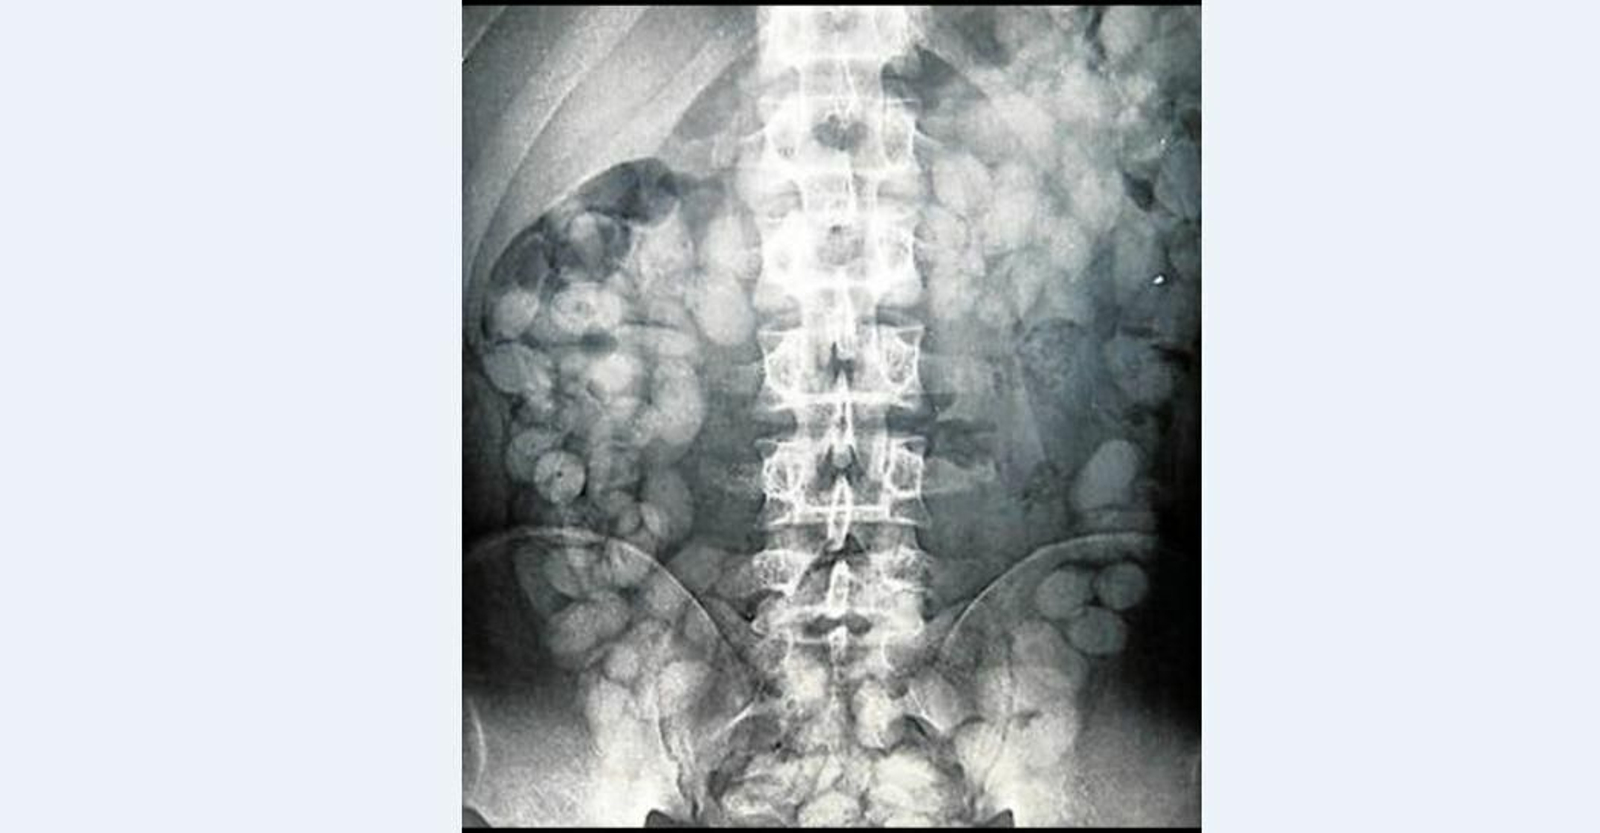

Radiografía en la que se observan las bellotas de hachís detectadas a un interno en la prisión de Botafuegos.

Acaip-UGT apunta que la droga se revaloriza entre la población reclusa, con ejemplos como que la heroína multiplica su valor por diez; la cocaína por cuatro o el hachís por cinco, según el sindicato. "En abril de este año se le requisó a un interno a la vuelta de un permiso de salida una bellota de heroína, otra de cocaína y 39 de hachís. Su valor en la calle sería de unos 1.500 euros mientras que alcanza los 6.000 entre los reclusos", apunta la central.